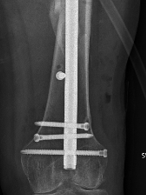

Nail

Iannacone et al J Orthop Trauma 1994

- 41 distal femur fractures treated with retrograde nail

- 4 non unions requiring revision fixation

- 4 fatigue fractures of the IMN; changed to using minimum 12 and 13 mm rods